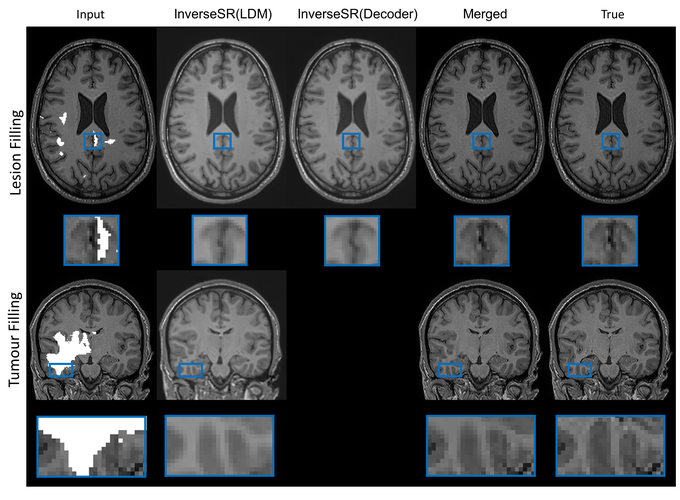

High-resolution (HR) MRI scans obtained from research-grade medical centers provide precise information about imaged tissues. However, routine clinical MRI scans are typically in low-resolution (LR) and vary greatly in contrast and spatial resolution due to the adjustments of the scanning parameters to the local needs of the medical center. End-to-end deep learning methods for MRI super-resolution (SR) have been proposed, but they require re-training each time there is a shift in the input distribution. To address this issue, we propose a novel approach that leverages a state-of-the-art 3D brain generative model, the latent diffusion model (LDM) trained on UK BioBank, to increase the resolution of clinical MRI scans. The LDM acts as a generative prior, which has the ability to capture the prior distribution of 3D T1-weighted brain MRI. Based on the architecture of the brain LDM, we find that different methods are suitable for different settings of MRI SR, and thus propose two novel strategies: 1) for SR with more sparsity, we invert through both the decoder of the LDM and also through a deterministic Denoising Diffusion Implicit Models (DDIM), an approach we will call InverseSR(LDM); 2) for SR with less sparsity, we invert only through the LDM decoder, an approach we will call InverseSR(Decoder). These two approaches search different latent spaces in the LDM model to find the optimal latent code to map the given LR MRI into HR. The training process of the generative model is independent of the MRI under-sampling process, ensuring the generalization of our method to many MRI SR problems with different input measurements. We validate our method on over 100 brain T1w MRIs from the IXI dataset. Our method can demonstrate that powerful priors given by LDM can be used for MRI reconstruction.